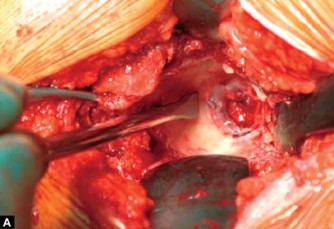

Introduction The basis of development of this chapter deals principally with the understanding of transtroc…